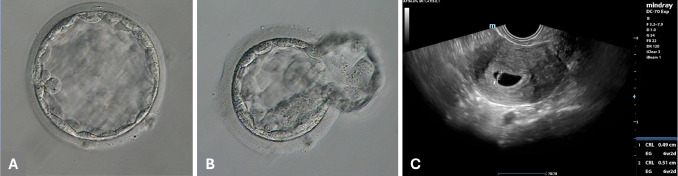

После культивирования эмбрионов было получено две бластоцисты, пригодные для переноса, в группе дистанционной ИКСИ, и две пригодные бластоцисты в контрольной группе. Все эмбрионы, за исключением одного, были витрифицированы. Для ранжирования эмбрионов использовался инструмент Искусственного интеллекта ERICA. Перенос "свежей" бластоцисты, полученной методом дистанционной ИКСИ (Рисунок 2А), которая имела наивысший ранг по оценке ERICA, не привел к наступлению беременности.

Последующий перенос витрифицированной-размороженной бластоцисты, полученной методом дистанционной ИКСИ (Рисунок 2В), со вторым по величине рангом, привел к концентрации β-ХГЧ в крови 61 мМЕ/мл на 25-й день цикла. Процедура дистанционной ИКСИ для этой бластоцисты была проведена из Хадсона, штат Нью-Йорк (США), на расстоянии около 3700 км от лаборатории ЭКО.

Ультразвуковое исследование, выполненное на 6-й неделе беременности, подтвердило наличие одного плодного яйца с сердцебиением плода (Рисунок 2С). Беременность протекала без осложнений, с нормальным ростом плода.